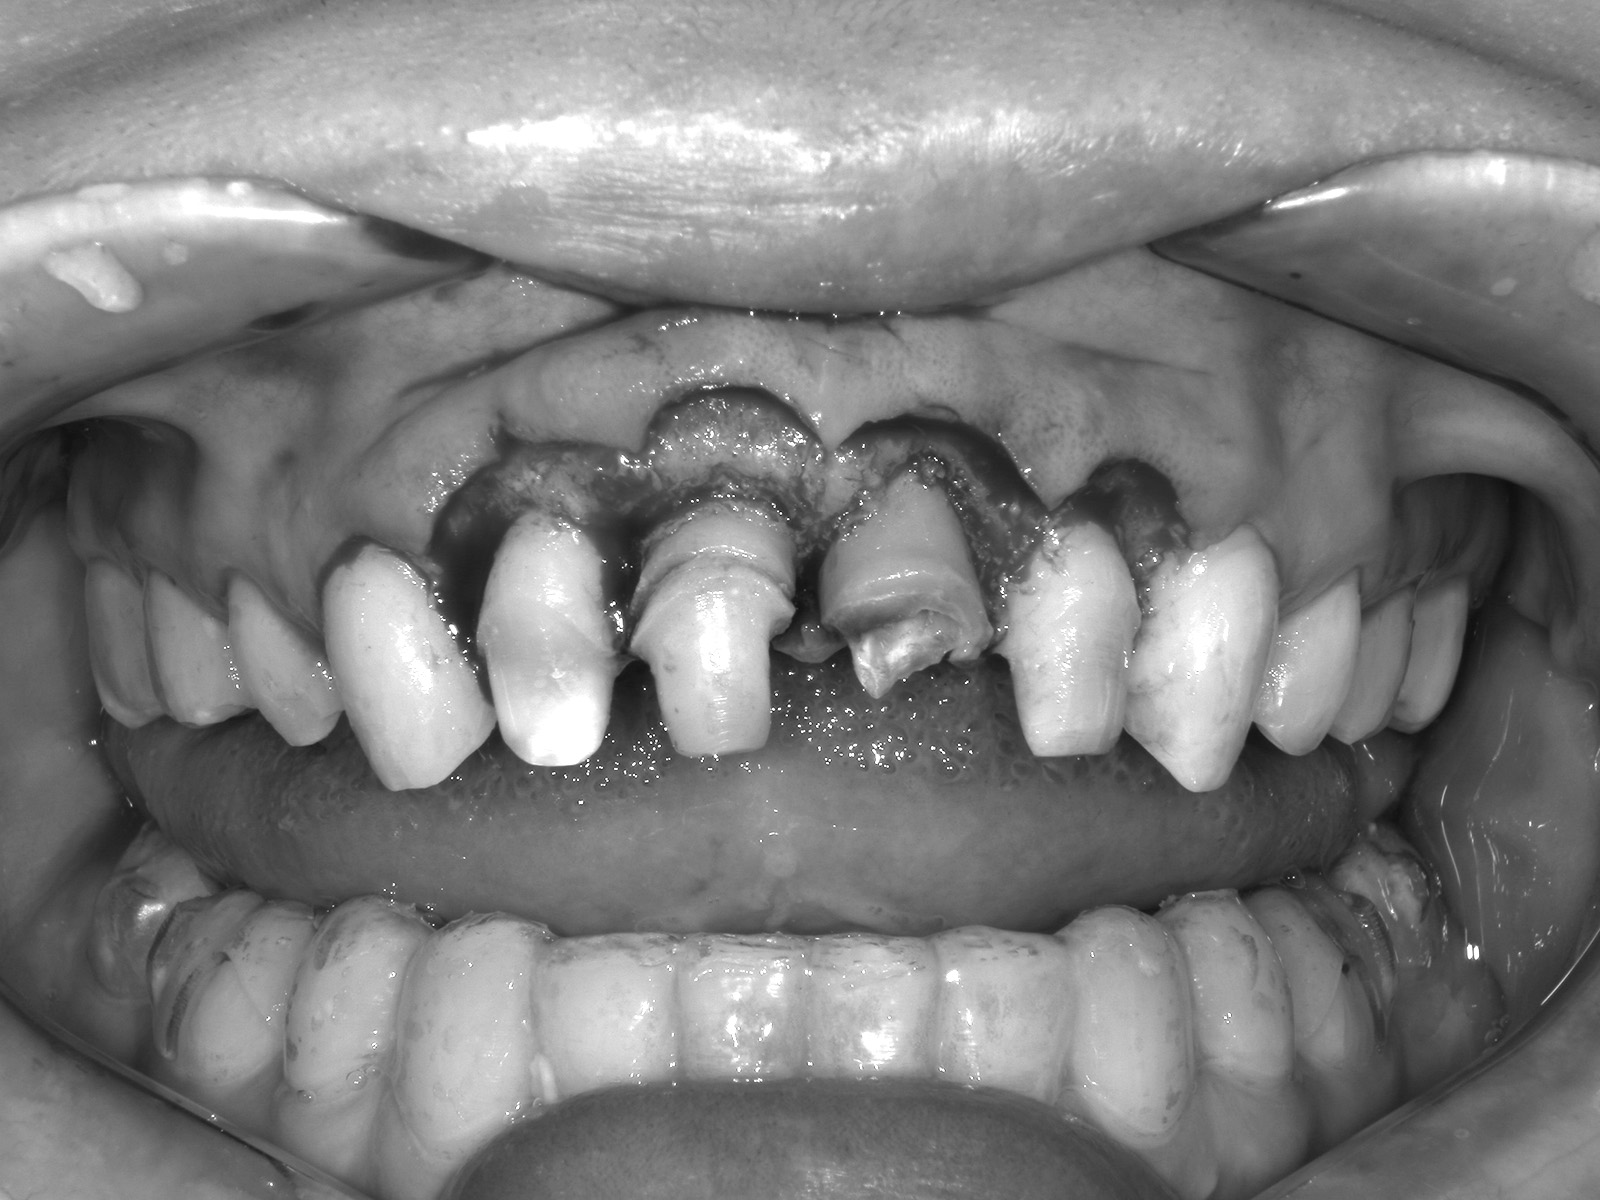

重度の虫歯や歯周病でも、すぐに「抜歯」とは判断せず、できる限り歯を残す治療を優先しています。

虫歯が進行して歯の頭が崩れてしまうと、被せ物を支える土台がなくなり、多くの歯科医院では抜歯を提案されることがあります。

しかし当院では、歯の根を少しずつ引き上げて健全な部分を露出させる「エクストルージョン法」により、歯を残せる可能性があります。

歯が大きく欠け、根だけが残った状態では、被せ物の装着が難しくなります。

このような場合に行うのが「クラウンレングスニング」です。

歯茎や周囲の骨を丁寧に削り、歯の根を十分に露出させることで、被せ物を安定して装着できるようにします。

歯の保存を第一に考える治療の一つです。

歯肉を切開し、歯根を露出させた状態。

被せ物を装着し、治療完了。